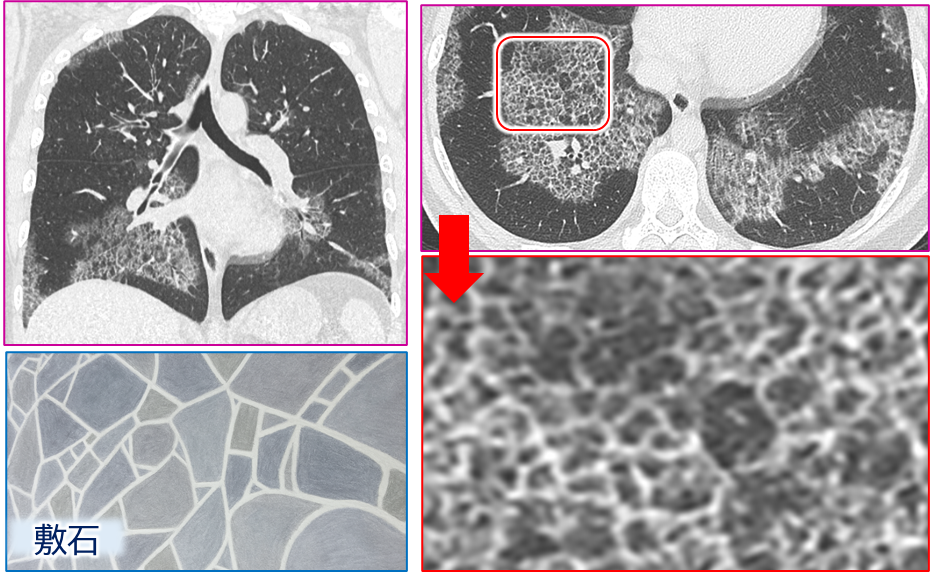

画像所見:「crazy paving」がキーワード

胸部CTの特徴

- 両側性、対称性のすりガラス影

- 小葉間・小葉内隔壁の肥厚

- 胸膜直下が保たれる(subpleural sparing)

これらが合わさって、いわゆる「crazy paving pattern」(敷石状パターン)を形成します。

- この所見は、自己免疫性PAPや遺伝性PAPで典型的です。

- 一方、びまん性のすりガラス影のみがみられるタイプもあり、特に他の原因によるPAPに多いです。

| Radiologic | – Central lung ground glass opacities with smooth interlobular and intralobular septal thickening in a crazy paving pattern. – Relative apical and costophrenic angle sparing | – 中枢領域にすりガラス様陰影がみられ、平滑な小葉間および小葉内隔壁の肥厚を伴い、「クレイジーペービング(敷石)パターン」を呈している。 – 相対的に肺尖部および肋骨横隔膜角は保たれている。 |